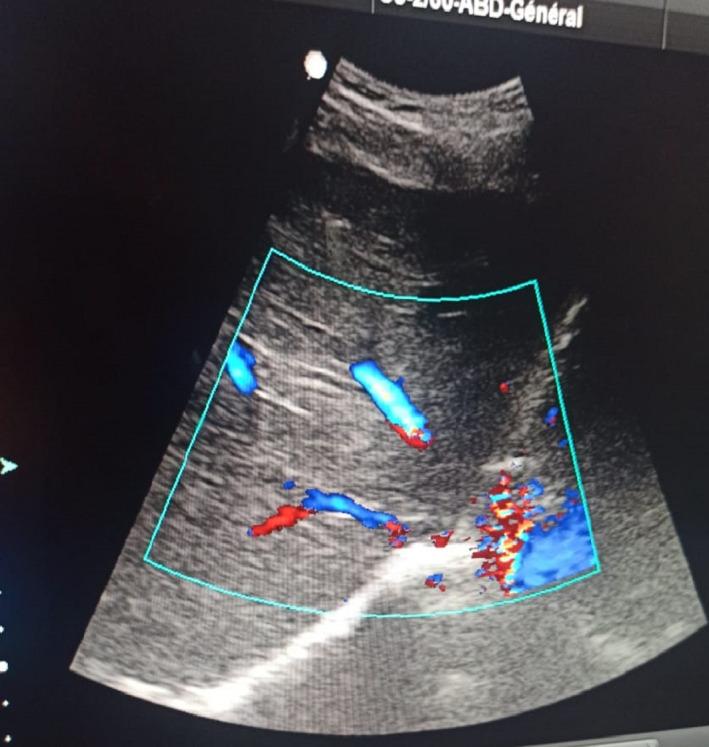

血浆置换治疗妊娠急性脂肪肝。

Plasma exchange as treatment for acute fatty liver disease of pregnancy.

Acute fatty liver disease of pregnancy AFLP is an obstetrical emergency, with severe complications that may include death. Management of AFLP is challenging and include plasma exchange which helps to improve the prognosis for both mother and fetus and delay liver transplantation.

摘要